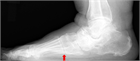

1. 分類は、変形のステージとタイプ分けからなる([1]。ステージは、足変形に可撓性があればⅠ、なければIIとする。変形のタイプはクラスAからクラスEの5つに細分され、クラスは単独あるいは複合することもある(表記例:ⅠA、IIABCIEなど)。(*日本足の外科学会用語委員会による和名)